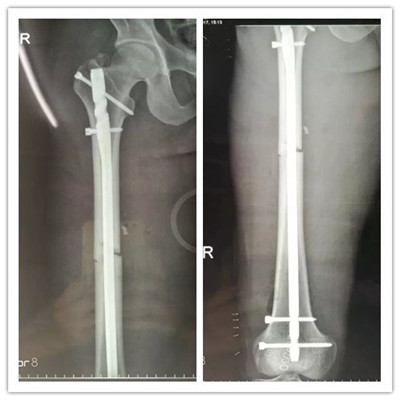

經(jīng)過慎重考慮和周密的術(shù)前計(jì)劃,羅軍主任帶領(lǐng)帶領(lǐng)科室團(tuán)隊(duì)用骨折閉合復(fù)位髓內(nèi)釘固定的微創(chuàng)方法為患者進(jìn)行手術(shù)。 近90分鐘的精心手術(shù),骨折處沒有切開,采用間接復(fù)位的方法就使骨折塊達(dá)到了解剖復(fù)位,并用微創(chuàng)切口導(dǎo)入髓內(nèi)釘對(duì)骨折進(jìn)行了牢固的固定,圍手術(shù)期沒有輸血,醫(yī)療費(fèi)用也明顯降低。

▲骨折的完美復(fù)位和內(nèi)固定